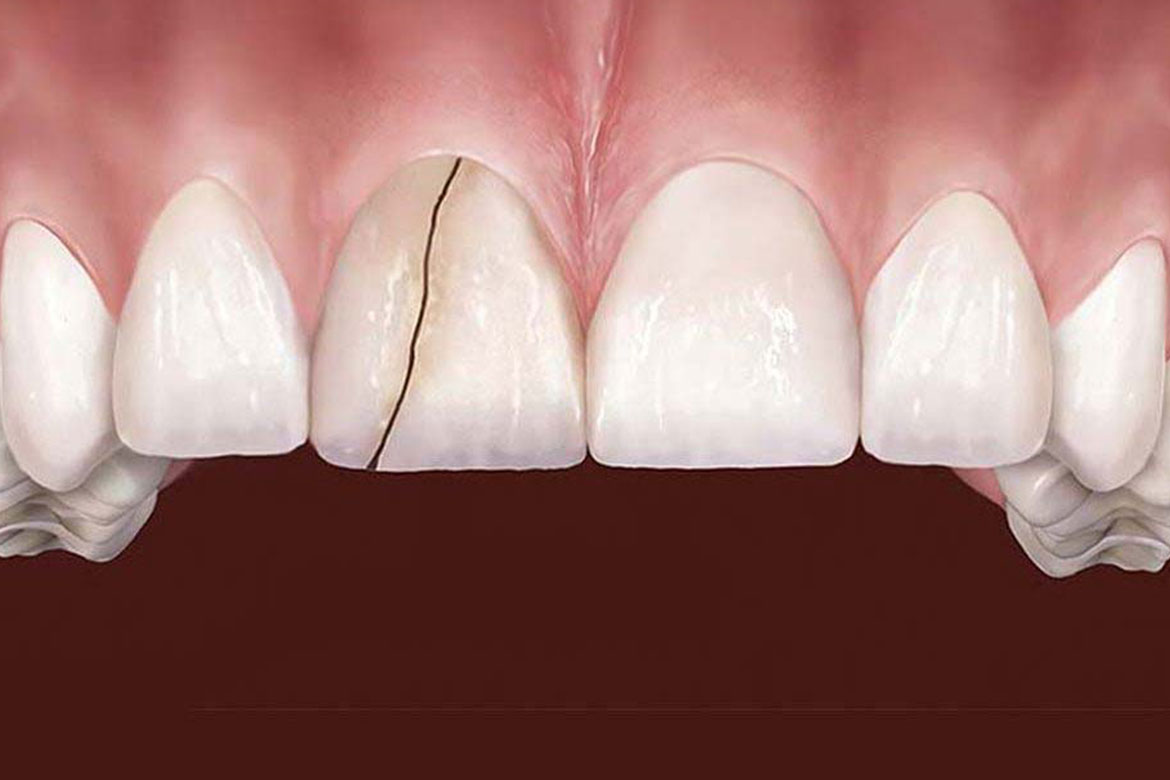

Syndrome de la dent fêlée (ou fissurée)